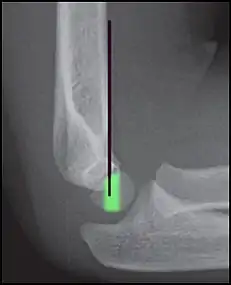

Anterior humeral line (black line), with normal area passed on the capitulum of the humerus colored in green in a 4 year old child.[8]